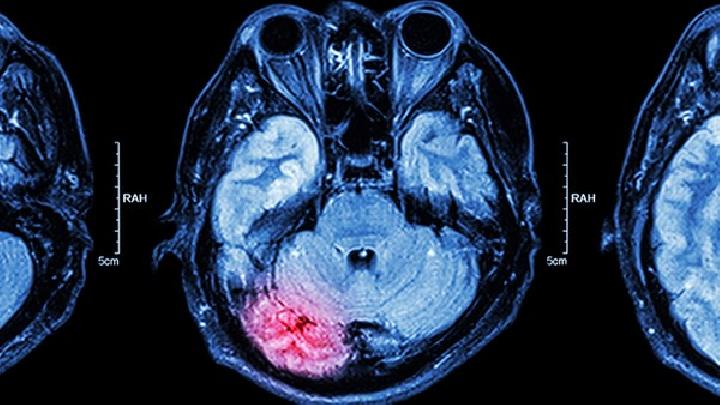

脑外伤后综合征

脑外伤后综合征是由什么原因引起的?

脑外伤